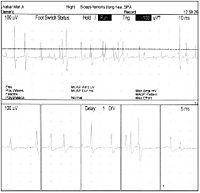

神经性肌强直的病因机制一直在探讨中。目前认为此病属钾通道异常而致的钾通道病中的一种具有高度普遍性和多样性的钾通道,是控制膜的去极化和细胞奋性的基础钾通道病的一个普遍特征是膜电位复极化的减弱 Kleman等认为神经性肌强直与慢钾通道传导的调节有关,它导致刺激后神经轴索兴奋阚值降低,去极化或超极化后兴奋性过度,持续时间延长面产生异常电活动,引起连续的运动单位括动=自发电括动的部位大多位于神经终束运动终板或运动轴索末梢分叉处,也可沿轴索全部或产生于运动轴索的某些近端区域的血一神经屏障内,甚至可累及前角运动细胞本身 。这种离子通道变化导致的运动轴索的过度兴奋,使受累肌肉出现颤搐、僵硬。肌电图所见高频自发性运动单位放电活动及成对的或多源的运动单位发放是神经性肌强直和肌纤维颤搐的特征性表现,提示了运动轴索的兴奋性特点:活检病理中可见少数肌纤维轻度萎缩,表明率病有周围神经损害。

本病的诊断主要依据为 :① 多在20岁左右起病,男性多见,少数有家族遗传史。② 临床特点为始自肢体远端的持续性肌纤维颤搐.明显时肌纤维收缩渡沿肌纤维纵轴方向呈波浪样前进,可伴肌松弛困难;运动后出现痛性肌僵硬.常伴过度出汗,休息后可缓解.睡眠时肌痉挛不消失③多为全身性可累及躯干、四肢肌肉,手足、面肌、跟睑肌、腹肌等亦可受累④ 可见肌肥大或萎缩,腱反射可因肌强直而减低或消失.无扣击性肌强直。⑤ 肌电图表现为自发持续性的运动单位放电活动。⑥苯妥因钠或卡马西平治疗效果良好。

神经性肌强直的主要表现为受累肌肉出现肌僵硬、痉挛、颤搐、无力和肌弛缓延迟,肌电图检出自发性持续性的运动单位放电活动。在休息状态下仍表现活跃的运动神经元电位,通常只有神经性肌强直和stiff-man综合征。

神经性肌强直所表现的病变部位可以是局部或全身,通常会影响面部和四肢,睡眠、神经阻滞、麻醉等手段无法阻止肌肉僵直,其中肌电图检查是较为重要的检查手段。